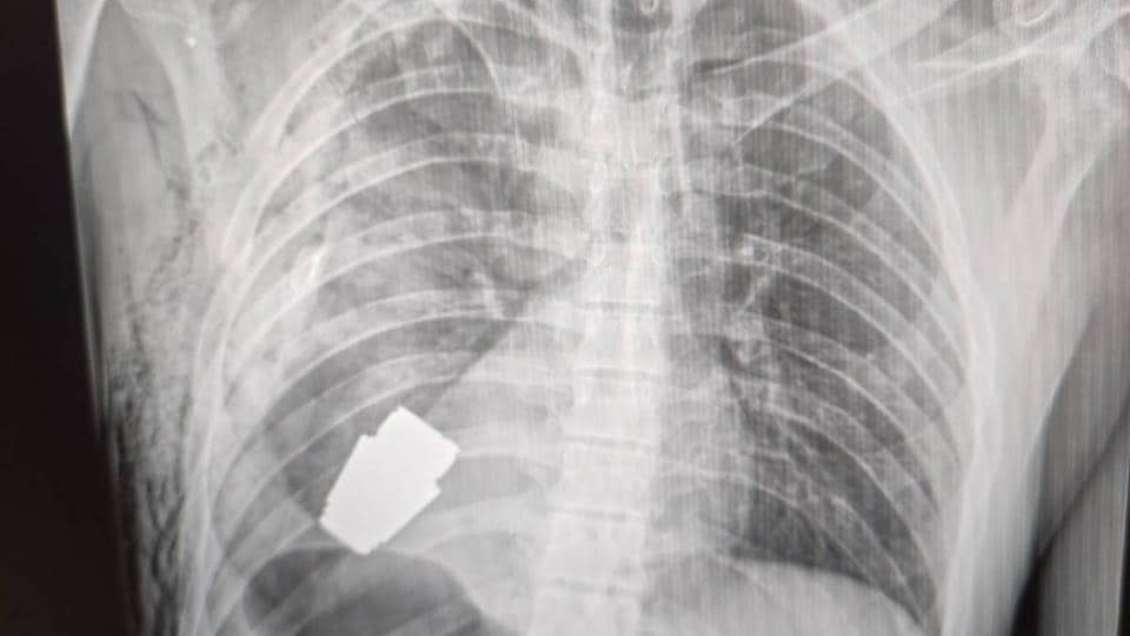

Un soldado ucraniano fue sometido a una exitosa cirugía para remover una granada sin detonar que estaba alojada en su pecho.

El asesor ministerial de asuntos internos de Ucrania, Anton Gerashchenko, aseguró que "la parte sin explotar de la granada fue extraída de debajo del corazón" y que si bien no explotó, "siguió siendo explosiva".